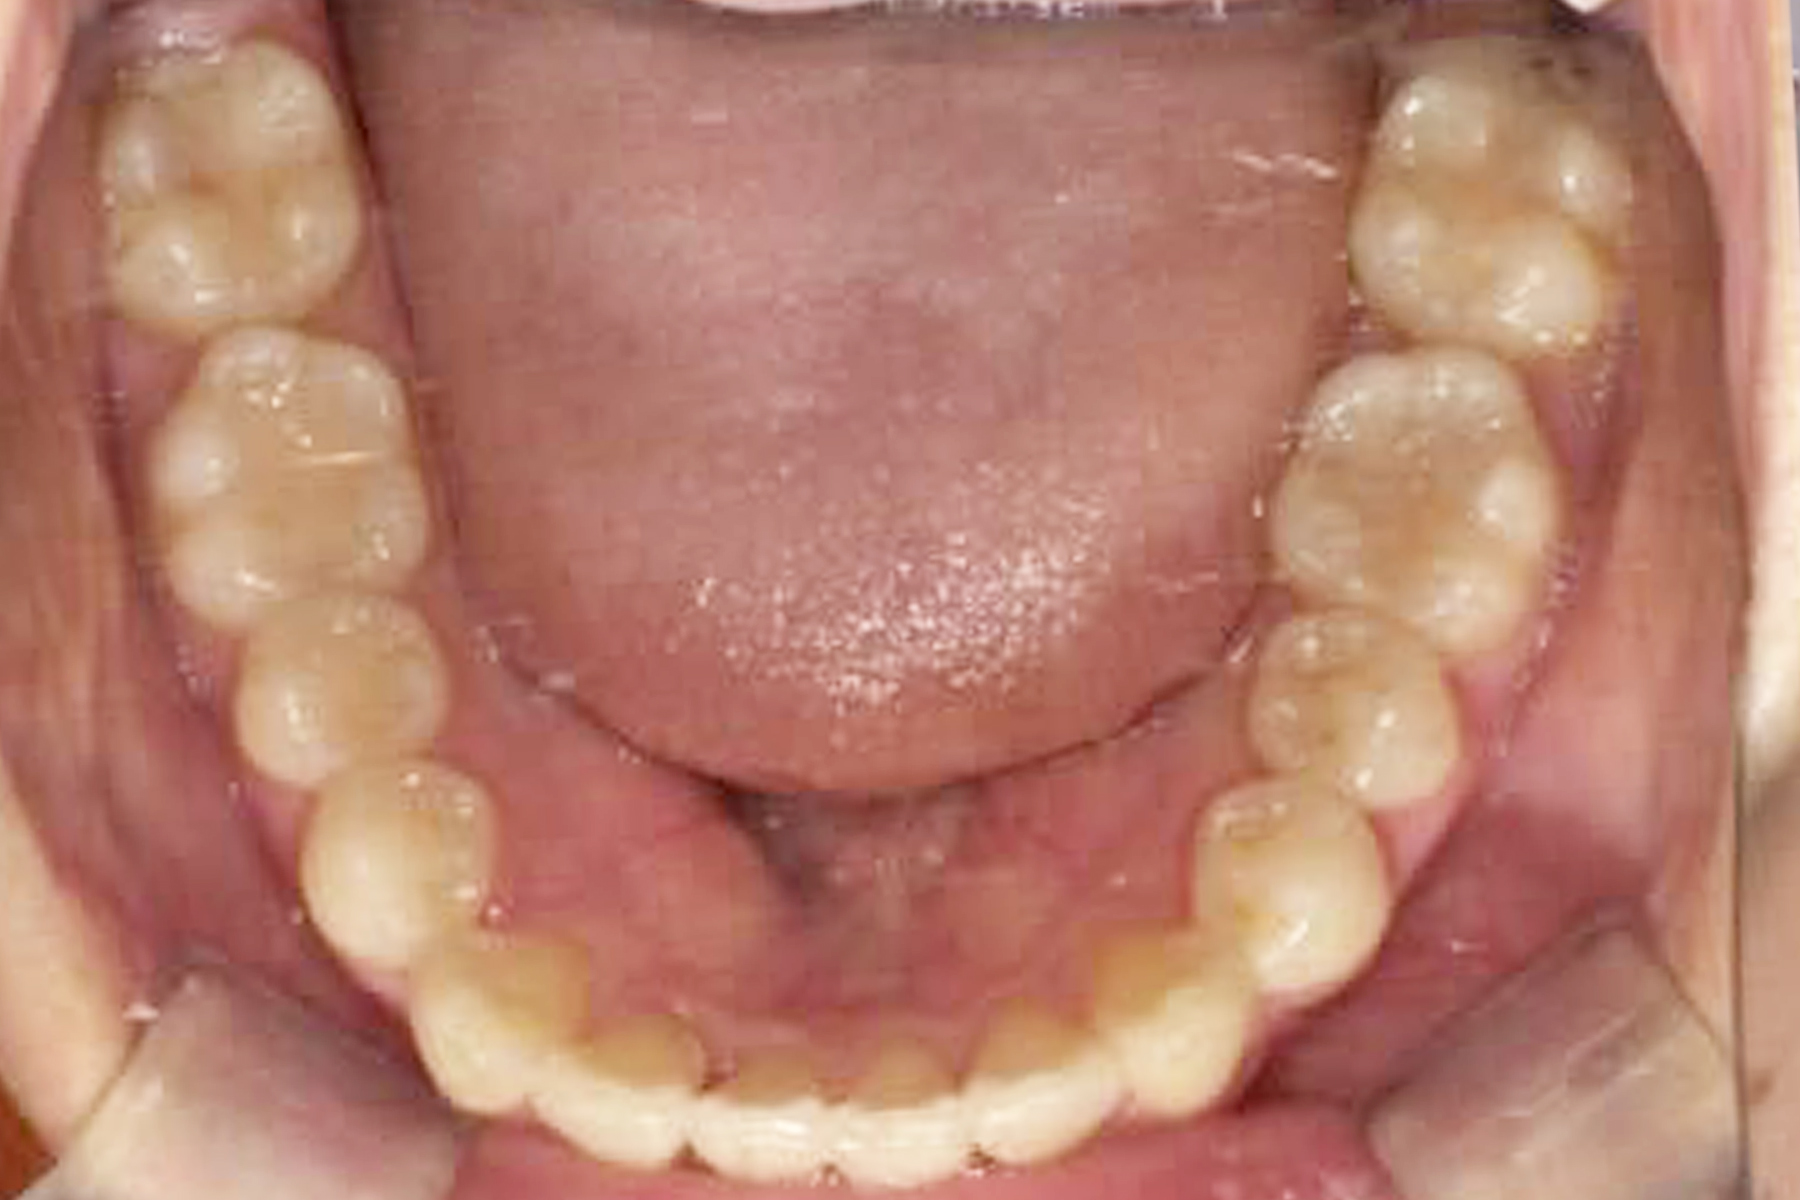

マウスピース矯正の症例

Case.1

BEFORE

AFTER

| 担当医 | 林 大貴 |

|---|---|

| 主訴 | 歯並びを直したい |

| 期間 | 約6ヶ月 |

| 費用 | 550,000円 |

| 治療内容 | マウスピース矯正 |

| 治療に伴うリスク | 動的治療後、保定装置を決められた期間確実に装着しなかったり した場合後戻りが起こる可能性があります。 |